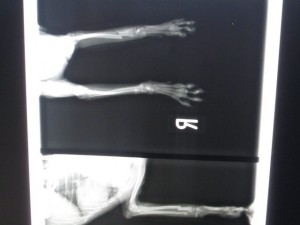

術前のレントゲンです。

左前肢橈尺骨骨折です。